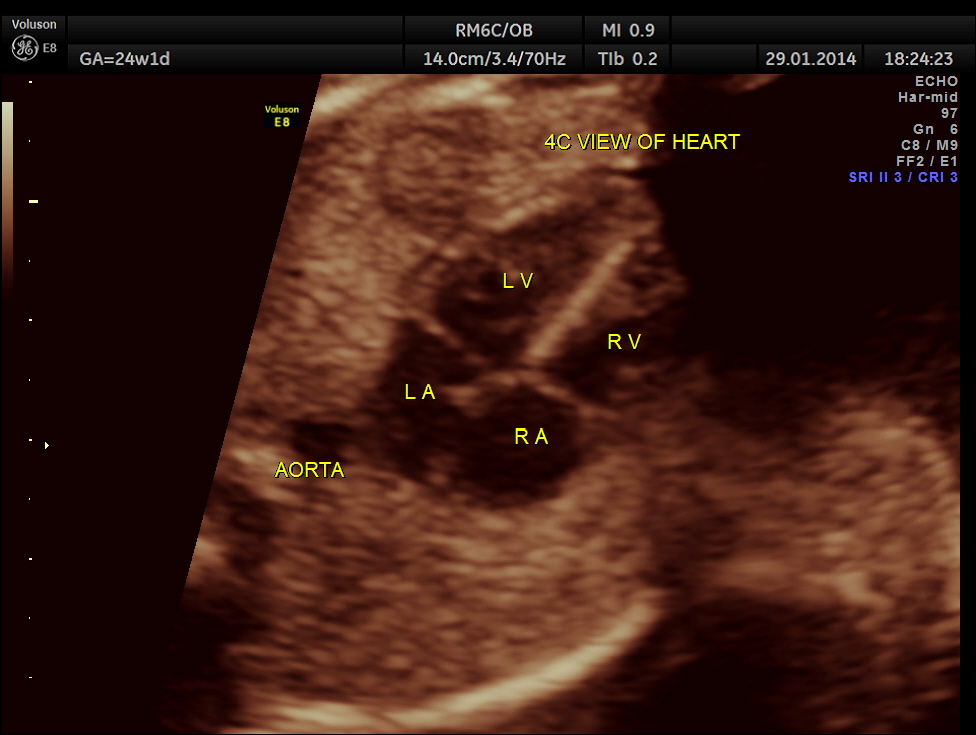

The 4 chamber view is abnormal – LV is smaller than RV.

The following pictures show that the left ventricle appears smaller than the right ventricle. The situs is normal.

A normal 3 vessel view and 4 chamber view are given below.